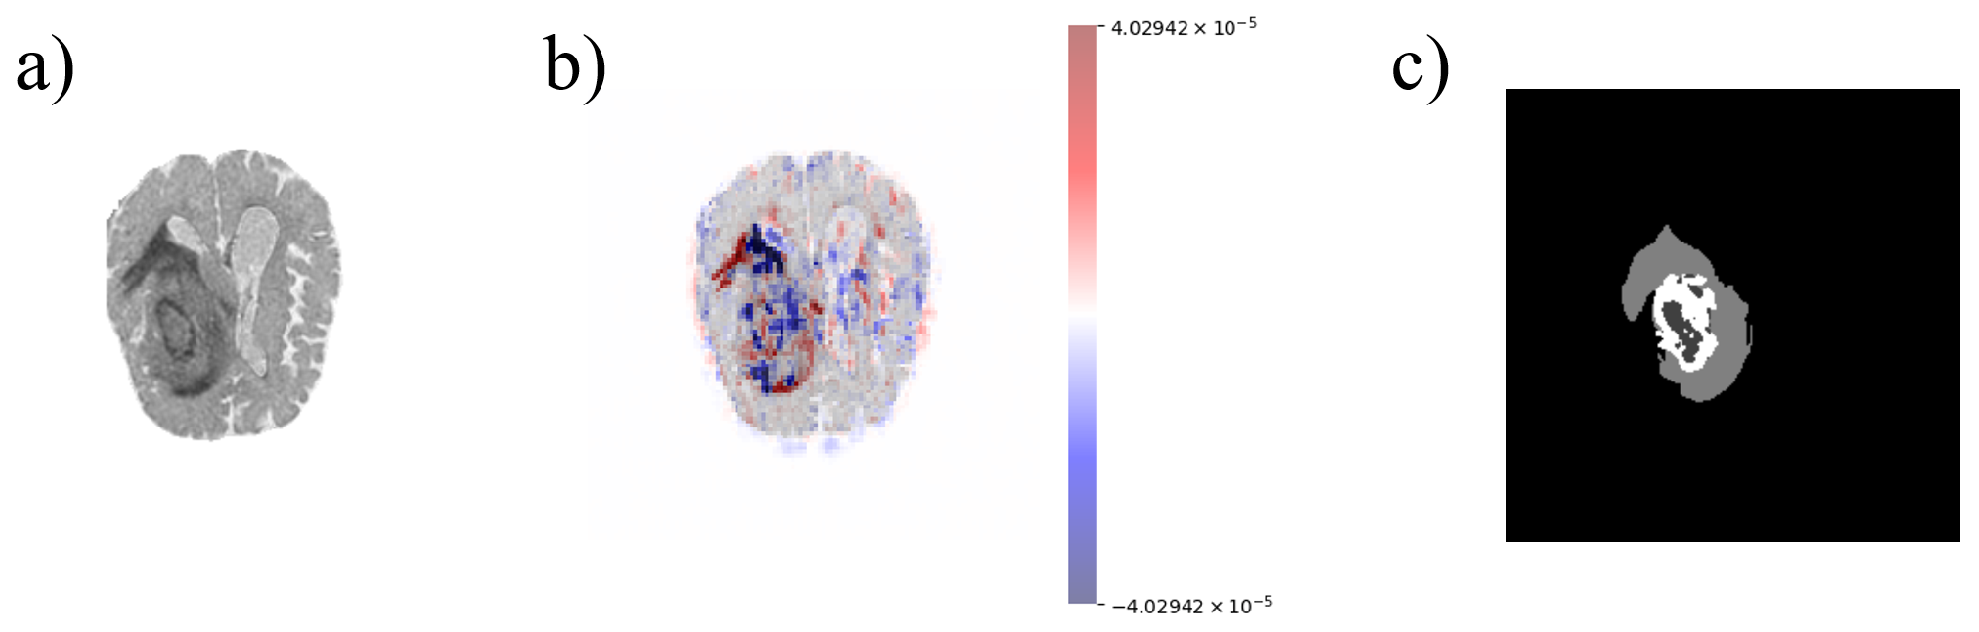

2.1. Data Pre-Processing

2.3. Explainability